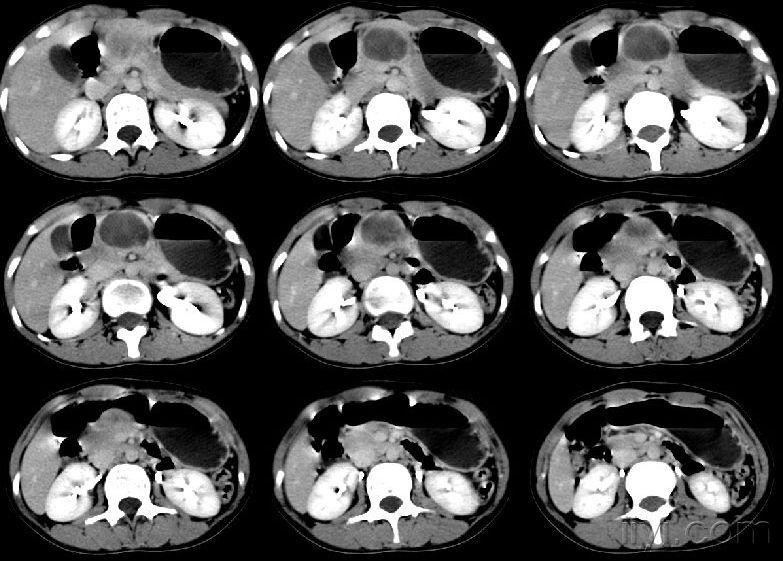

胰腺钩突部占位

紧急求助胰腺钩突部占位

胰头钩突区低密度占位性病变

横切貌似胰头占位,但是细心看看钩突部的显示